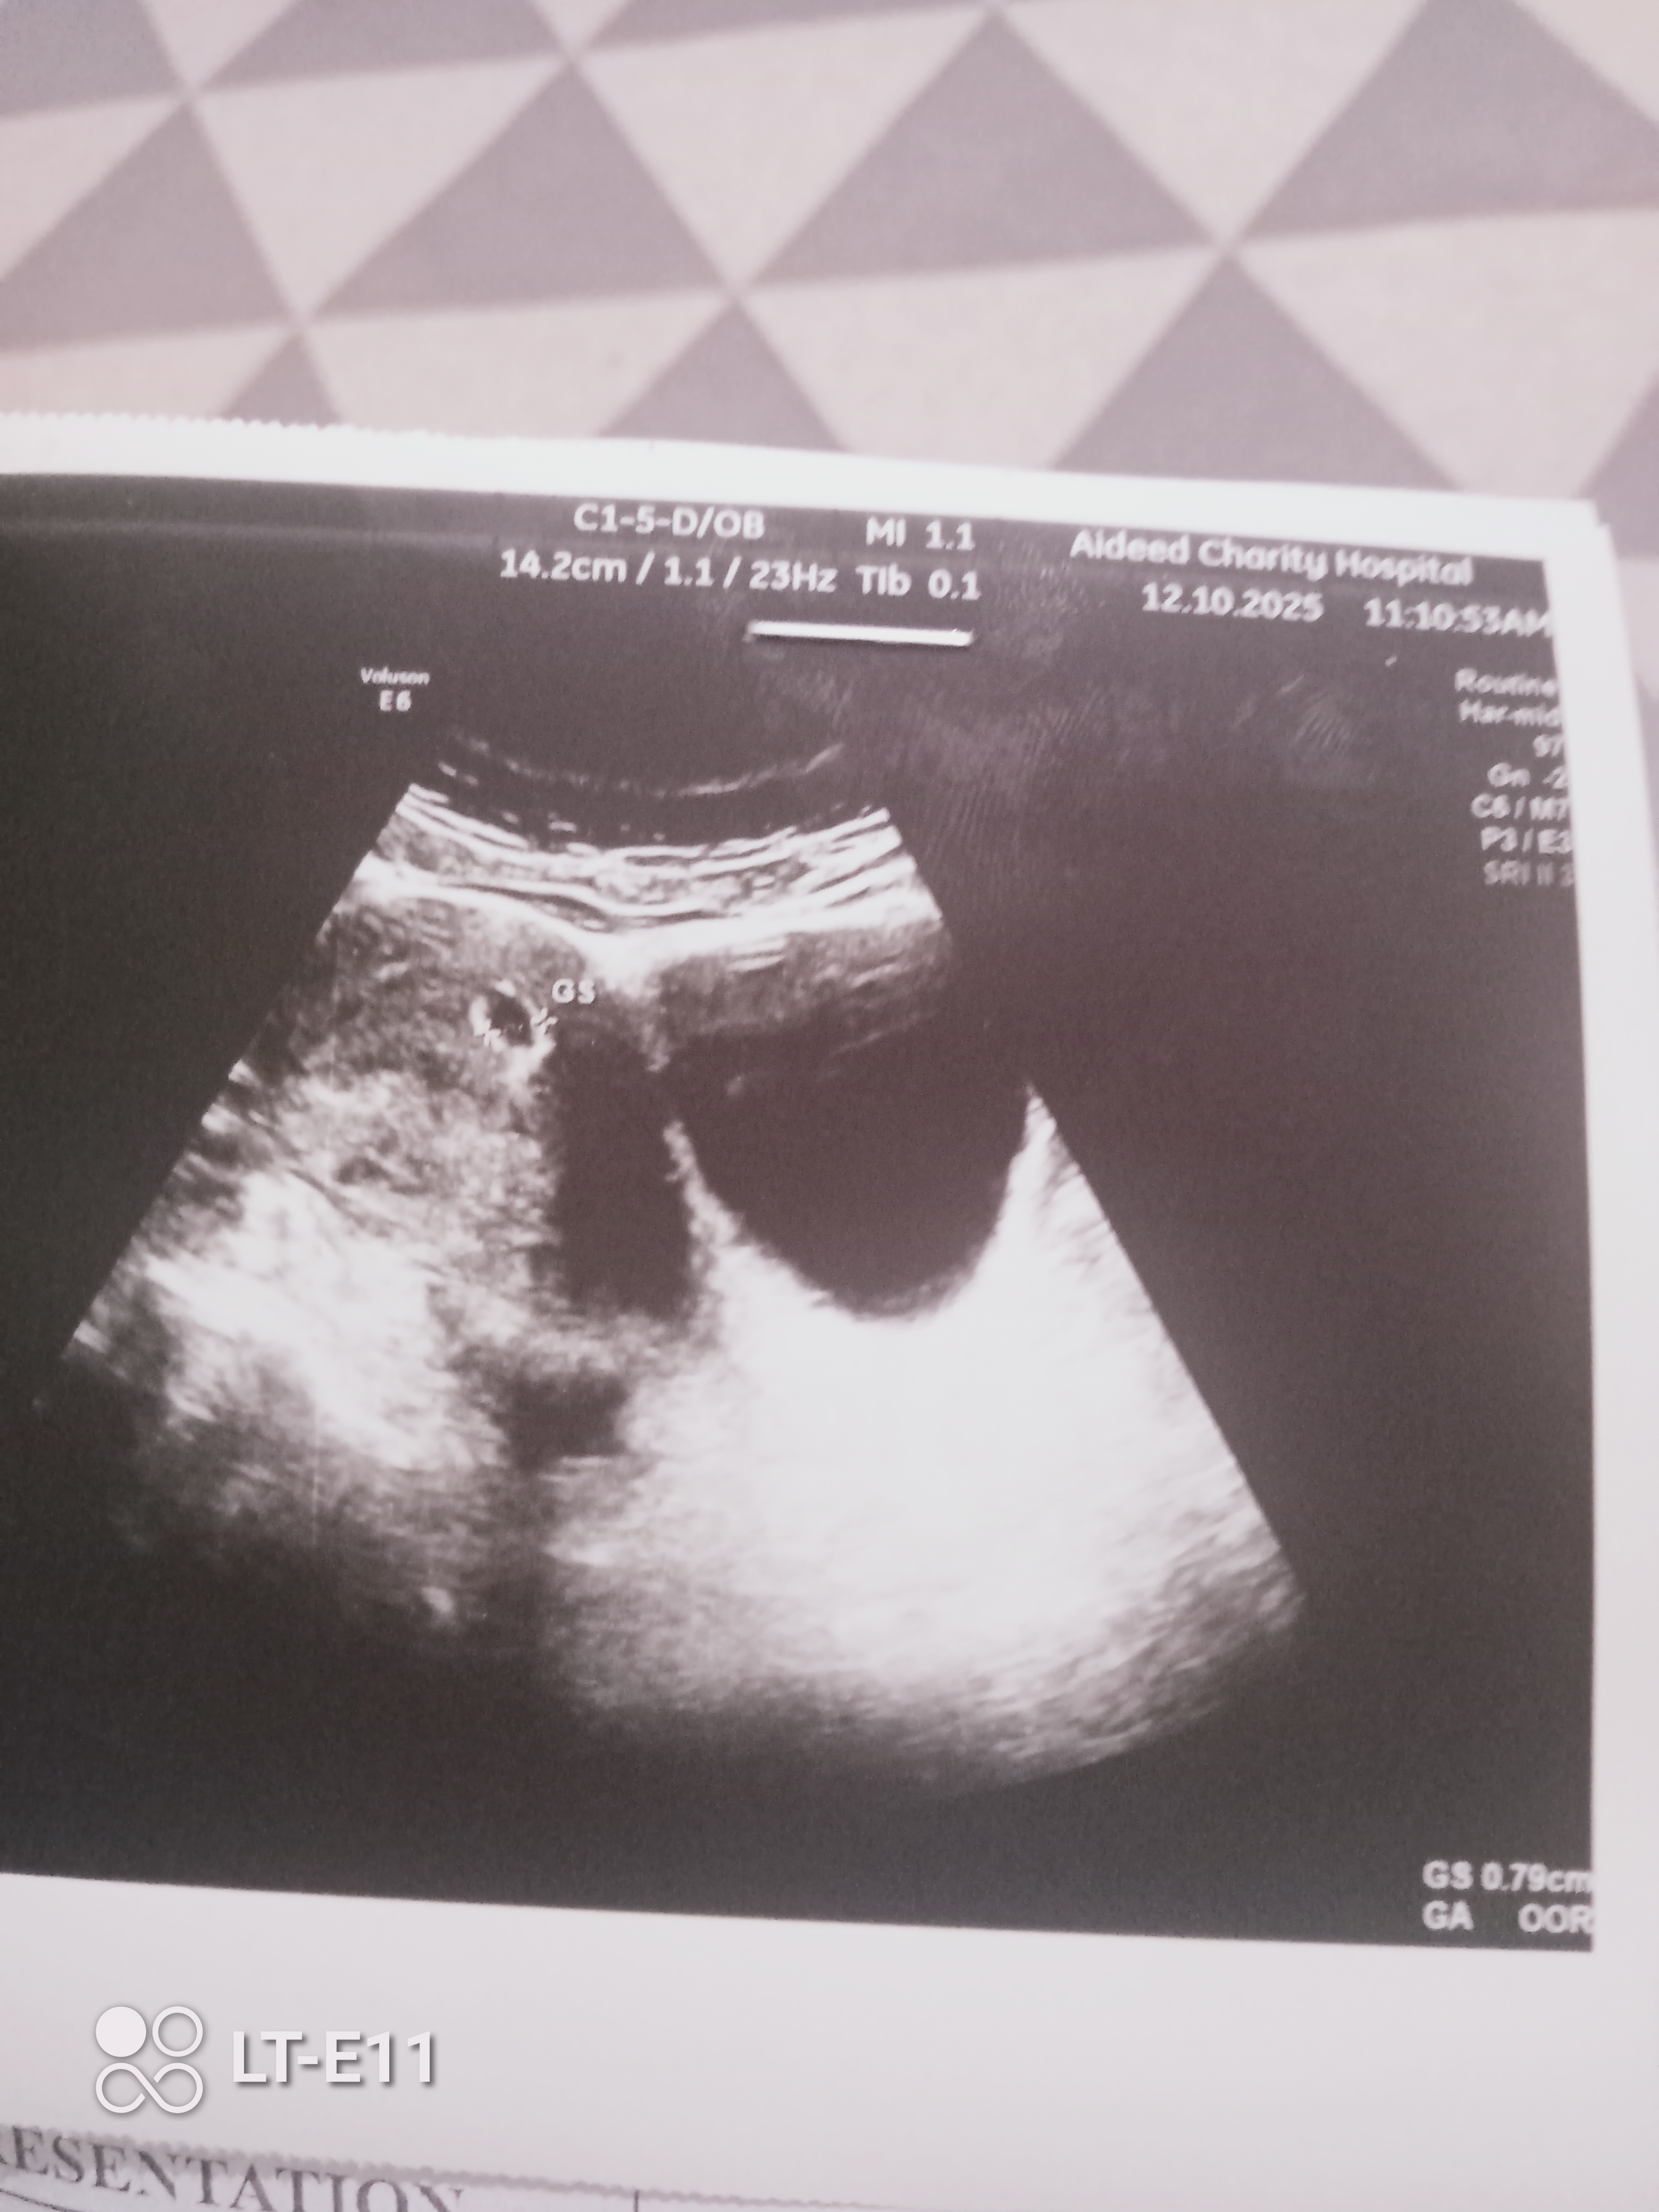

انا حامل بالاسبوع الخامس والطبيعة قالت ان جدار الرحم ضعيف